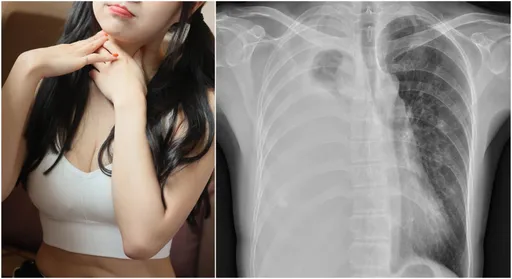

...嚴重,轉而到醫院就診,經過詳細檢查、篩檢,確認感染黴漿菌肺炎,X光還呈現大片反白,證實罹患「會走路的...

...0到急診,X光檢查顯示有兩側輕微肺炎,且肺癌黴漿菌檢驗陽性,診斷為黴漿菌肺炎,住院後使用抗生素治療。